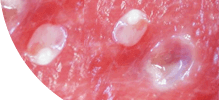

- Паразитларни фалаж қилади ва тухумларини 48 соат ичида йўқ қилади

- Токсинларни бутунлай йўқ қилади ва 1-2 ой ичида танани тиклайди